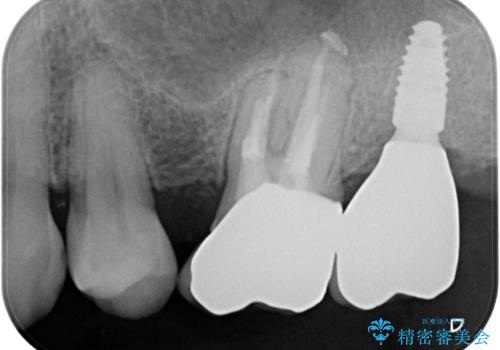

奥の歯は抜歯が必要なため、インプラント埋入による補綴治療を行うこととしました。

手前の歯は状態は良くないものの、抜歯するほどではないと判断したため、根管治療後にオールセラミッククラウンにて補綴治療を行うこととしました。

術後半年でレントゲン写真を撮影したところ、インプラント周りの骨は安定しており、根管治療を行った歯周辺の病変はきれいに改善されていました。